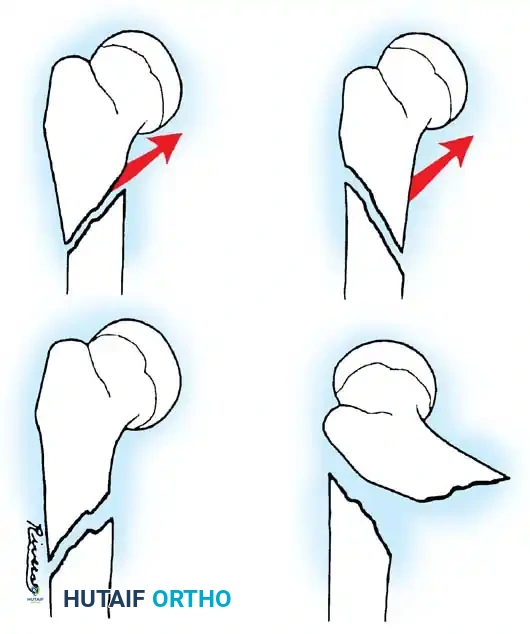

Fig. 33-146: Subtrochanteric fracture stability. (A) If the proximal spike of bone is posterior, the fracture is often stable against the distal fragment. (B) Conversely, if the proximal spike is anterior, the fracture is highly unstable, and 90-90 traction or operative fixation is necessary to counteract the flexion force of the iliopsoas.